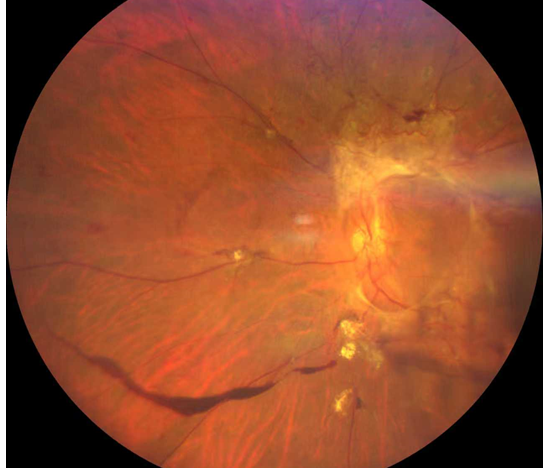

雙眼被確診為Ⅱ期增殖性糖尿病視網(wǎng)膜病變(以下簡(jiǎn)稱“糖網(wǎng)”),并伴有黃斑水腫。

糖尿病視網(wǎng)膜病變

這意味著,如果再晚來(lái)幾天,視網(wǎng)膜損傷將不可逆轉(zhuǎn),他將永遠(yuǎn)失去光明。